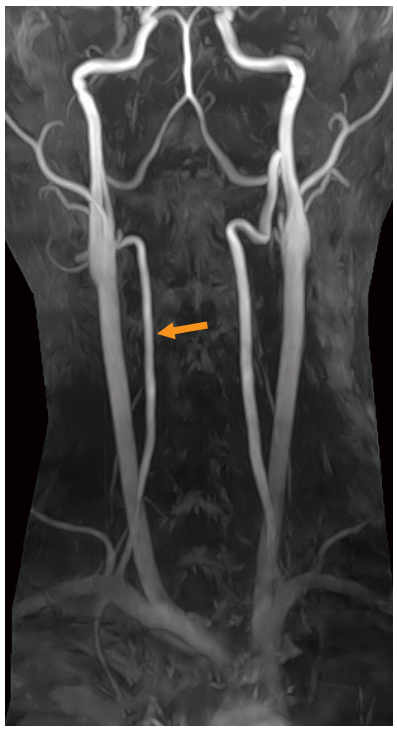

頸部MRA像を示す。

矢印で示すのはどれか。

- 外頸動脈

- 総頸動脈

- 椎骨動脈

- 内頸動脈

- 脳底動脈

解説

答え 3